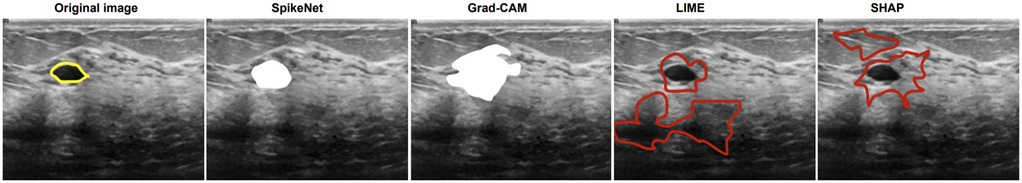

We compare explanation methods using the XAlign metric, which scores spatial alignment between saliency maps and expert annotations. To control for backbone effects, all post hoc methods (Grad-CAM, LIME, SHAP) are applied to the SpikeNet classifier with the native explanation head disabled and target the last convolutional block for Grad-CAM. The row labelled SpikeNet (native) reports the integrated explanation head with the head enabled. All results follow the same preprocessing and patient-level evaluation protocol. Each figure illustrates the explanation maps generated for a representative image, accompanied by the expert-annotated tumour boundary (yellow). Additionally, XAlign scores are reported to quantitatively measure the alignment between the saliency maps and ground truth. Tables 1114 report XAlign for representative MRI and ultrasound cases; dataset-level means with standard deviations and paired tests are provided in Table 15 later in this section.

Figure 3 shows the results on a BUSI ultrasound image. SpikeNet demonstrates superior precision with a clean, well contained explanation. Grad-CAM identifies the tumour but shows spatial diffusion, while LIME and SHAP fail to localize the tumour effectively. Quantitative scores in Table 13 highlight SpikeNet’s dominance with a near-perfect score of 0.931.

Figure 3

Five ultrasound images of the same area, each demonstrating different image processing techniques. The original image highlights a section in yellow. The SpikeNet image displays a white highlighted region. Grad-CAM shows a different white highlighted area. LIME outlines in red around two regions. SHAP highlights multiple red-bordered areas, varying in size and shape.

Figure 3. Visual comparison of explanation maps generated for a representative BUSI ultrasound image. The original image shows the expert-annotated tumour boundary (yellow), along with explanation maps from SpikeNet (white), Grad-CAM (white), LIME (red), and SHAP (red).